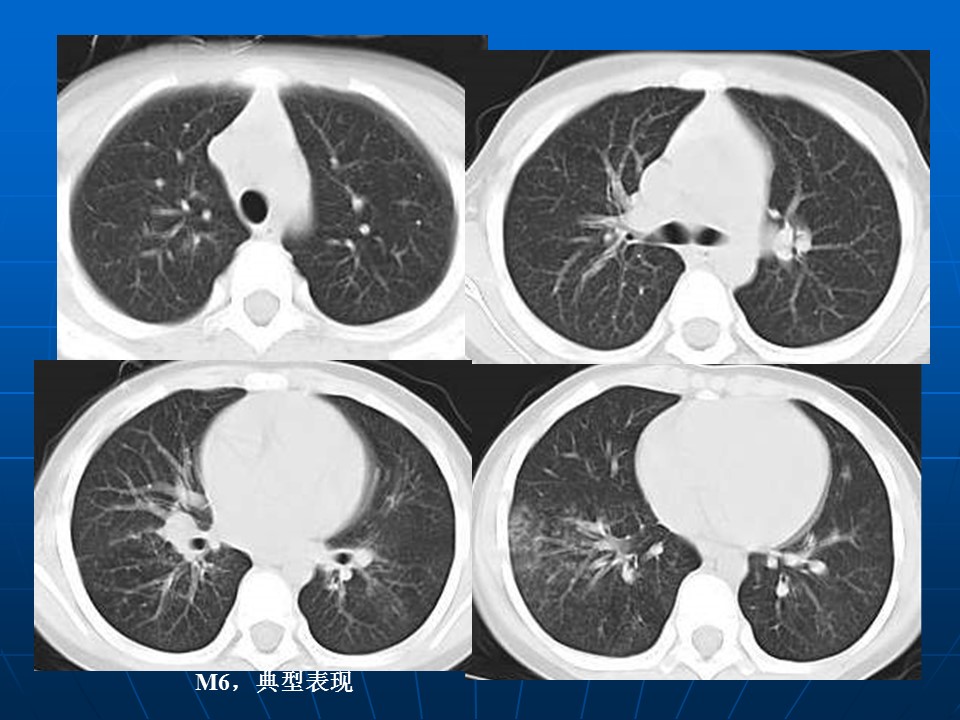

【病例】矽肺1例CT影像表现